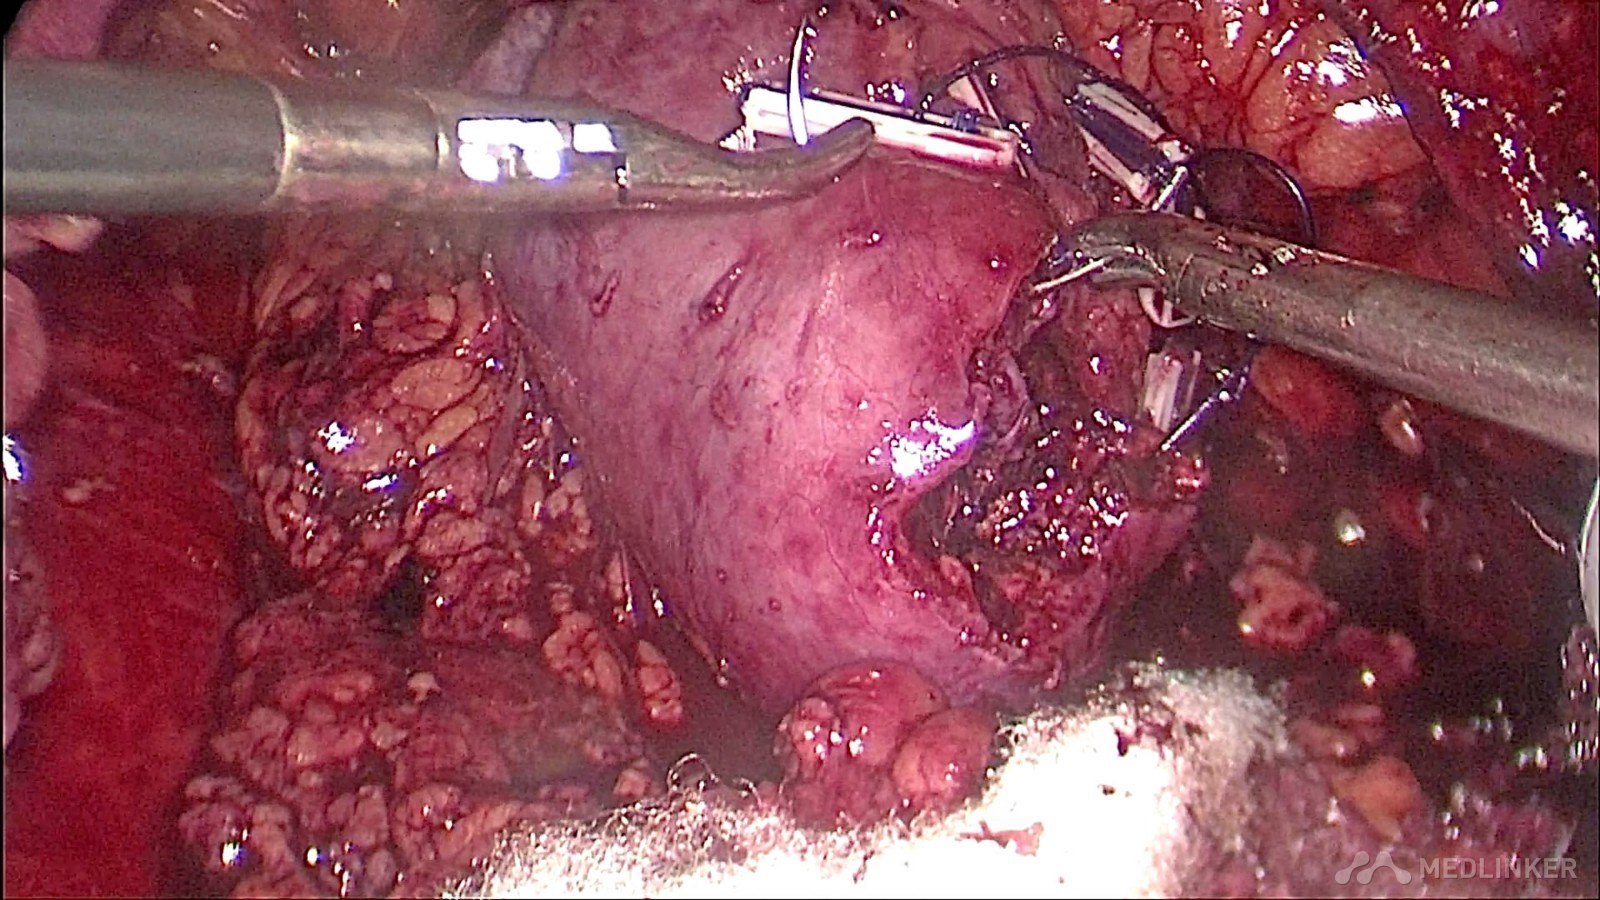

充分游离右肾动脉及分支,阻断血流,防止大出血的发生,降低输血几率

完整切除分叶状肿瘤

术中快速病理提示为右肾错构瘤